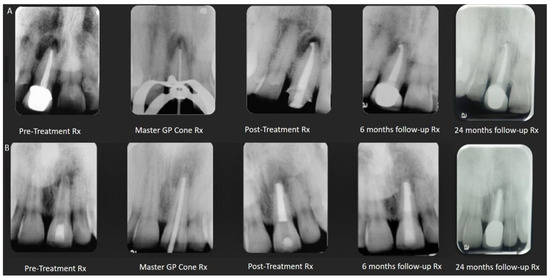

2.4. Resorptions

2.5. Non-Divergent Open Apex